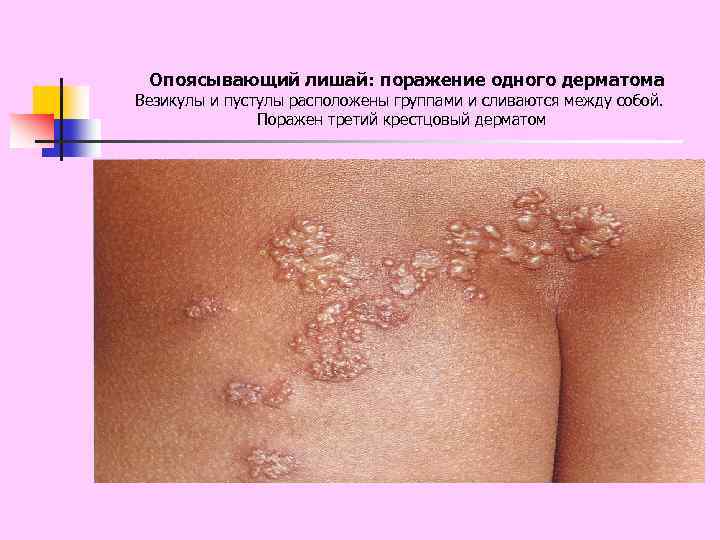

Опоясывающий лишай: поражение одного дерматома Везикулы и пустулы расположены группами и сливаются между собой. Поражен третий крестцовый дерматом

Опоясывающий лишай: поражение одного дерматома Везикулы и пустулы расположены группами и сливаются между собой. Поражен третий крестцовый дерматом